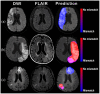

Introduction: In Acute Ischemic Stroke (AIS), mismatch between Diffusion-Weighted Imaging (DWI) and Fluid-Attenuated Inversion-Recovery (FLAIR) helps identify patients who can benefit from thrombolysis when stroke onset time is unknown (15% of AIS). However, visual assessment has suboptimal observer agreement. Our study aims to develop and validate a Deep-Learning model for predicting DWI-FLAIR mismatch using solely DWI data.

Patients and methods: This retrospective study included AIS patients from ETIS registry (derivation cohort, 2018-2024) and WAKE-UP trial (validation cohort, 2012-2017). DWI-FLAIR mismatch was rated visually. We trained a model to predict manually-labeled FLAIR visible areas (FVA) matching the DWI lesion on baseline and early follow-up MRIs, using only DWI as input. FVA-index was defined as the volume of predicted regions. Area under the ROC curve (AUC) and optimal FVA-index cutoff to predict DWI-FLAIR mismatch in the derivation cohort were computed. Validation was performed using baseline MRIs of the validation cohort.

Discussion and conclusion: The model accurately predicts DWI-FLAIR mismatch in AIS patients with unknown stroke onset. It could aid readers when visual rating is challenging, or FLAIR unavailable.